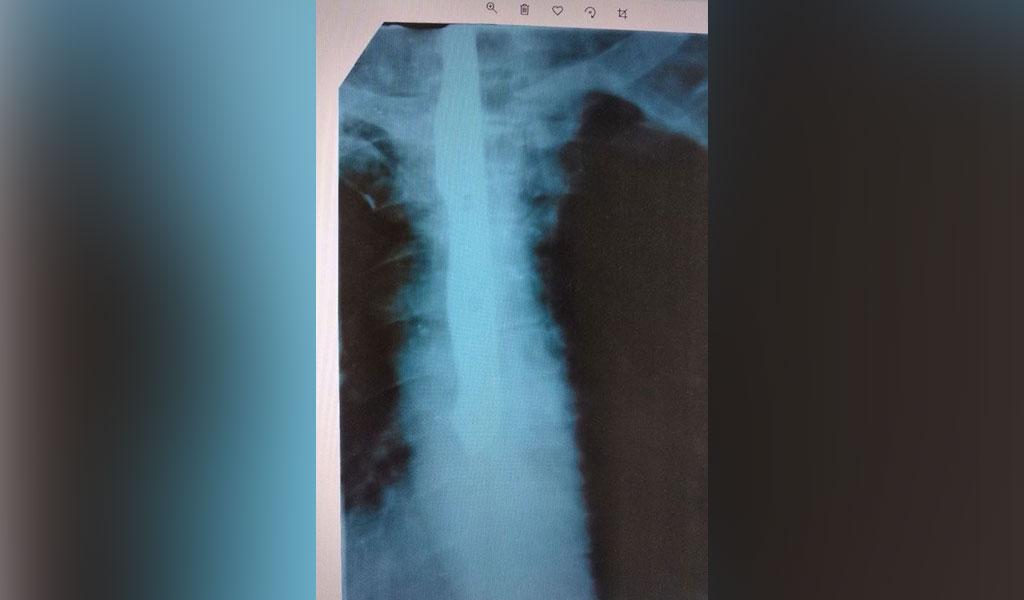

Տղամարդը դիմել է հիվանդանոց՝ կոկորդում առկա ցավերից գանգատվելով: Ռենտգենյան ճառագայթով ստացված նկարում հաջողվել է տեսնել 23 սանտիմետրանոց խոհանոցային դանակ, որը մխրճված է եղել հիվանդի կերակրափողի մեջ: Թե ինչպես է այն այնտեղ հայտնվել, տղամարդը ոչ մի կերպ չի կարողացել բացատրել: